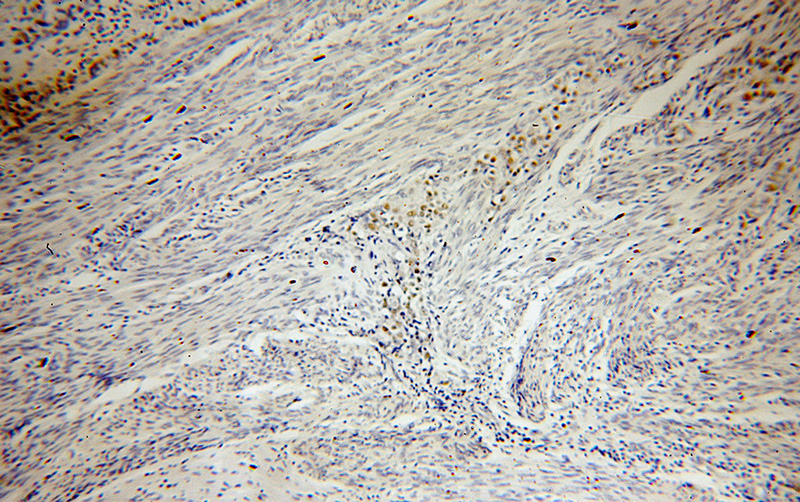

Immunohistochemical of paraffin-embedded human endometrial cancer using Catalog No:113553(P53 antibody) at dilution of 1:100 (under 10x lens)

Immunohistochemical of paraffin-embedded human endometrial cancer using Catalog No:113553(P53 antibody) at dilution of 1:100 (under 40x lens)